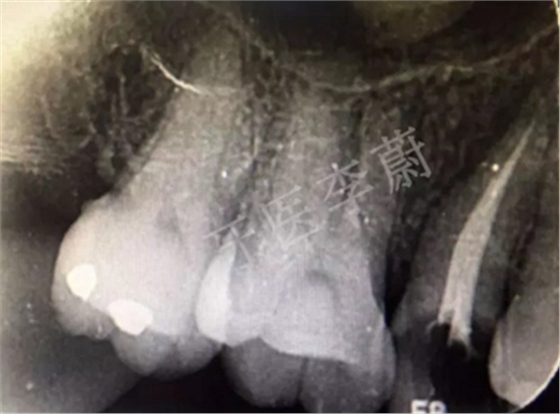

15牙根管充填術(shù)后X牙片

15牙根管預(yù)備試尖片